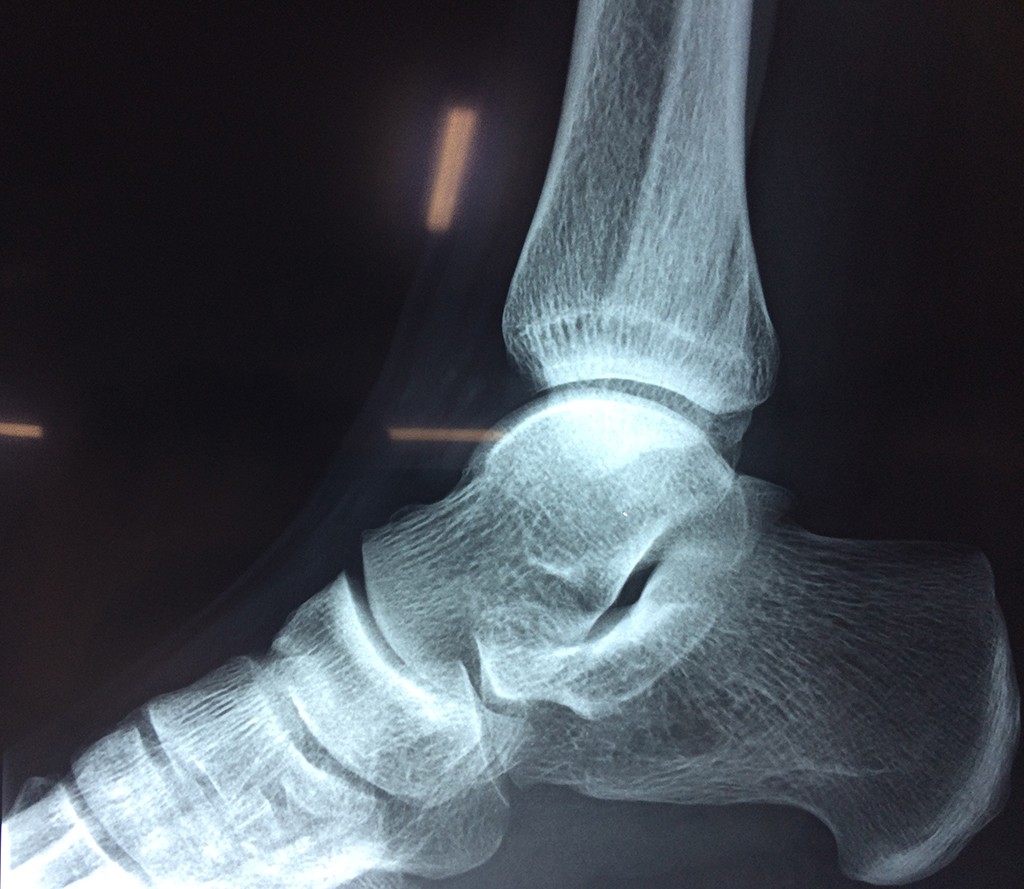

Una fractura de tobillo es la rotura de uno o más de los huesos del tobillo. Estas fracturas pueden ser:

- Parciales (el hueso está sólo parcialmente fisurado, no del todo).

- Completas (el hueso está perforado y está en 2 partes).